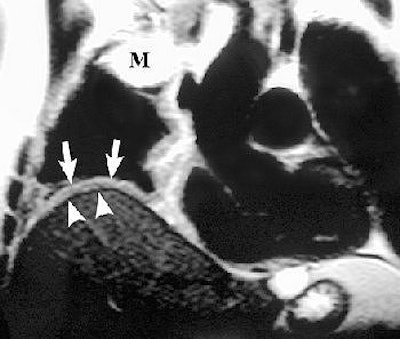

![]() |

Sagittal T1-weighted (above) and coronal T2-weighted (below) MR images show the mass with involvement of the diaphragmatic pleura (arrows). However, there is no invasion of the diaphragmatic muscle itself (arrowheads). Figure 16, Wang ZJ, Reddy GP, et al, "Malignant Pleural Mesothelioma: Evaluation with CT, MR Imaging, and PET" (RadioGraphics 2004; 24: 105-119).

On T1-weighted MR images, malignant pleural mesothelioma (MPM) is typically isointense or hyperintense. On T2-weighted images, MPM is moderately hyperintense. In both cases, gadolinium enhances the disease, they added.

MRI may also prove superior for assessing the growth of MPM, either as an invasion of the diaphragm, invasion of the endothoracic fascia, or a single chest wall focus.